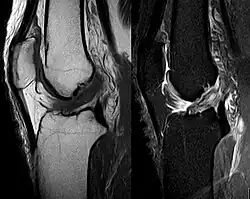

Procédés d'imagerie

Le diagnostic peut être confirmé par imagerie (IRM). Mais il faut noter que l'interprétation de l'IRM seule pour le diagnostic de rupture de LC conduit à 20 % de faux diagnostics. Cela dépend des images de coupe et de la position appropriée du genou pendant l'IRM. Le radiologue doit connaître avec précision les circonstances qui ont conduit à la blessure, et avoir aussi une bonne expérience de l'étude d'une articulation blessée, pour éviter les faux diagnostics. Pour comparer avec l'IRM, le taux d'erreur du test de Lachman, bien plus simple à accomplir, n'est que de 10 %[108],[109],[110],[111]. L'IRM est donc généralement moins sensible et moins spécifique que l'examen clinique par un orthopédiste qualifié[112]. Le résultat de l'IRM n'a que relativement rarement une influence sur la formulation finale du diagnostic[113] et ne devrait pas servir de remplacement pour une anamnèse soigneuse et la palpation[114]. Plusieurs études arrivent à la conclusion que l'IRM n'a de sens que pour des blessures complexes difficiles à expliquer, et là, pour éviter de poser un diagnostic négatif[115],[116],[117].

Arthroscopie diagnostique

La sécurité diagnostique la meilleure est obtenue par arthroscopie diagnostique. Ce procédé représente l'étalon-or pour le diagnostic de la rupture de LC. Ce procédé relève d'une chirurgie invasive au minimum, mais comporte certains risques, comme toute intervention chirurgicale dans le genou du patient[118]. Comme cependant le traitement chirurgical d'une rupture de LC sera conduit par chirurgie arthroscopique, il est possible d'enchaîner celle-ci immédiatement après l'arthroscopie diagnostique, par la résection partielle du ligament (pour une déchirure) ou la reconstruction en cas d'arrachement. Avec l'accroissement de la facilité de l'IRM, le nombre d'arthroscopies purement diagnostiques a nettement diminué ces dernières années[119],[120]. L'arthroscopie diagnostique est quand même utilisée comme précédemment comme procédé de choix pour une compréhension certaine du diagnostic de rupture de LC, en cas d'examen clinique confus et d'IRM difficile à interpréter[118].